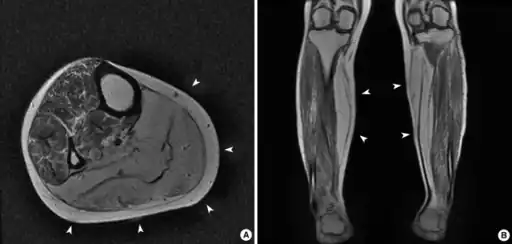

a,b)Predominant atrophic and fatty changes of bilateral gastrocnemius and soleus muscles (arrow)

The diagnosis of this condition can be done via muscle biopsy[5]